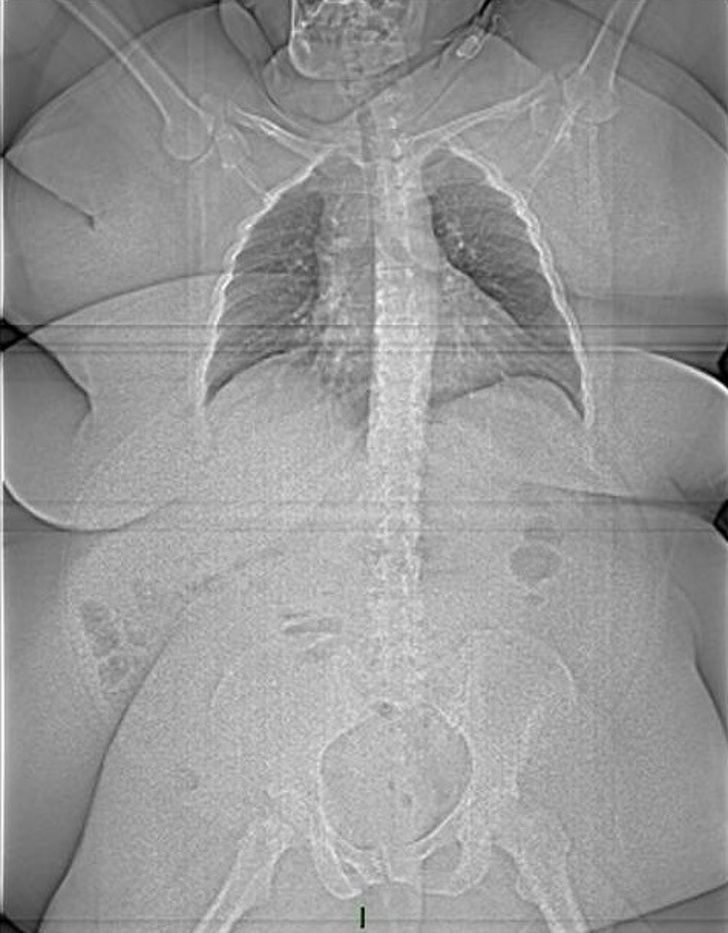

We can spend hours and hours reading books on anatomy to learn more about our body but what’s more eye-opening are a series of MRI scans and X-rays that precisely shows our body.